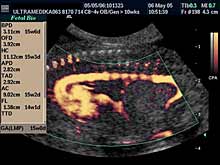

Radi adekvatne procene postojanja anatomskih anomalija pored Broadband

2D se koristi i 3D Sono CT i 3D CPA organskih sistema dostupnih

pregledu. 3D mekih tkiva lica je sastavni deo ultrazvučnog pregleda u

ovoj gestacionoj starosti. c)

- 3D Sono CT SRCA PLODA (fetalna ehokardiografija) Prostorno, vremenska

korelacija ultrazvučnih markera prikazana multiplanarno predstavlja

dopunsku metodu u otkrivanju urođenih srčanih anomalija.

- Radi povećane tačnosti ultrazvučnog pregleda radi se 3D Sono CT mozga,

kičme, srca, abdominalnih organa ploda, i mekih tkiva lica i

ekstremiteta, kao i 3D CPA procena cirkulacije ploda. Nakon